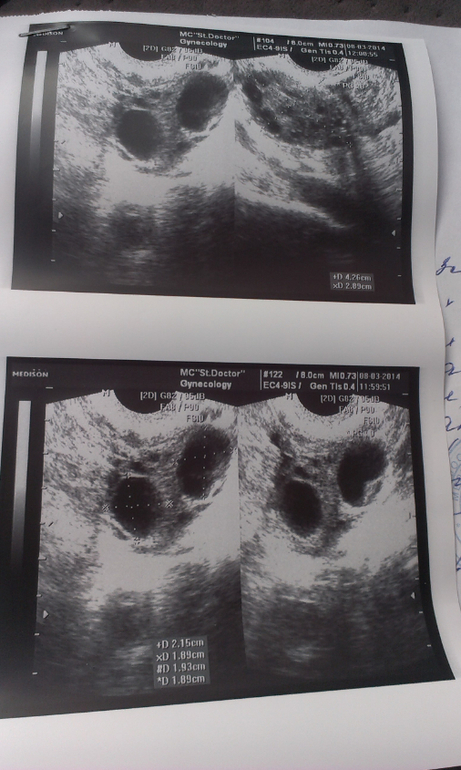

Желтое тело на УЗИ

Желтое тело можно обнаружить во время диагностической процедуры, если УЗИ пришлось на период сразу после овуляции. Это подтверждает, что цикл овуляторный и сама овуляция прошла нормально.

Желтое тело можно увидеть на трансабдоминальном и трансвагинальном УЗИ органов малого таза. Для женщин, живущих половой жизнью, более точным вариантом будет трансвагинальное исследование.

На экране аппарата врач УЗИ увидит неоднородное округлое образование. Появляется желтое тело в правом или левом яичнике в зависимости от локализации созревания доминантного фолликула и овуляторной яйцеклетки. Сторона созревания не имеет принципиального значения для будущей беременности и здоровья женщины.